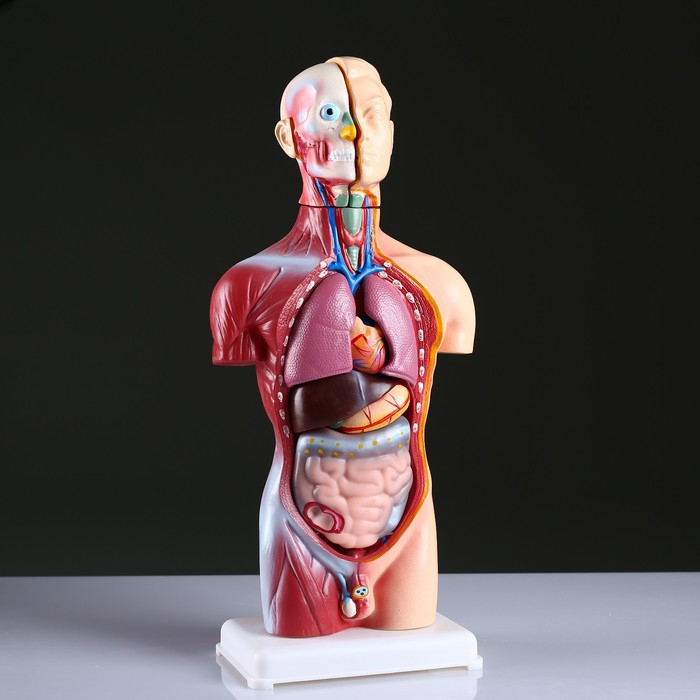

Анатомические модели